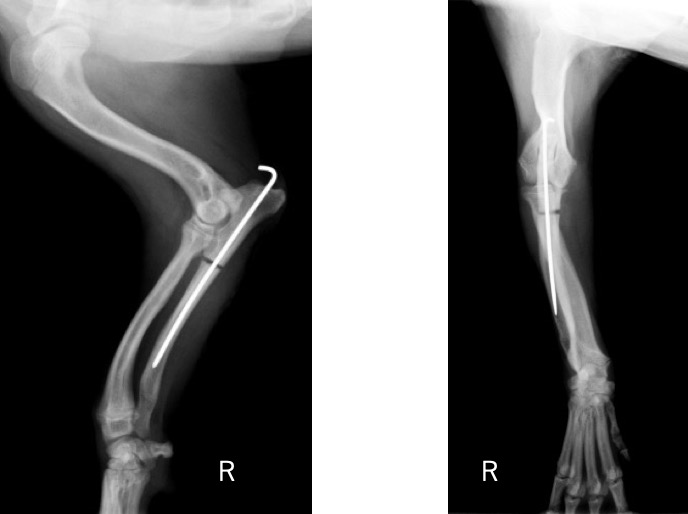

前腕のLateral像とAP像 (黄丸と黄矢印:成長板の不透過性亢進 赤矢印:上腕骨顆と肘突起の間隙)

術後のLateral像とAP像 (前例と同じく髄内ピンとしてK-wireを刺入したのちに切り取った骨片を破砕し、骨切部分へ再移植しました。)